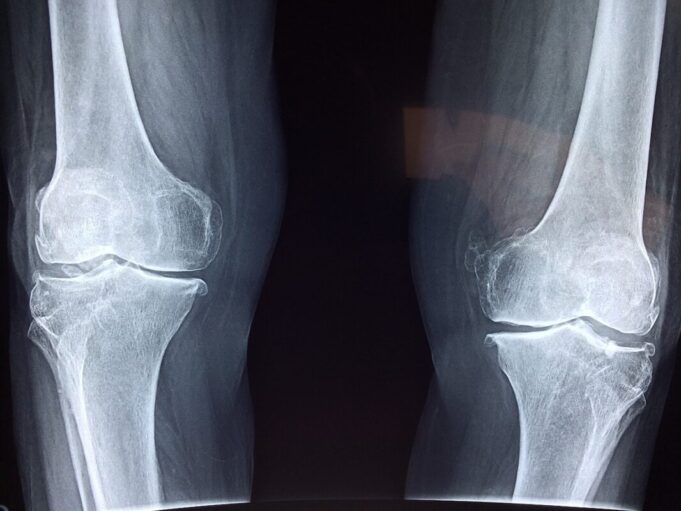

Les personnes âgées et souffrant d’ostéoporose sont particulièrement touchées, mais ils ne sont pas les ...